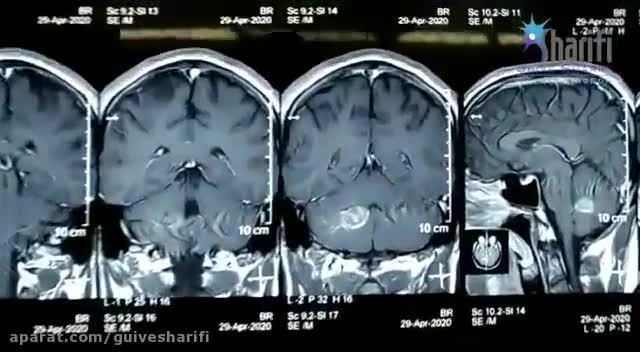

174. فیلم جراحی کاورنوس آنژیوما مخچه دکتر گیو شریفی

دکتر گیو شریفی (جراح مغزو اعصاب و ستون فقرات )